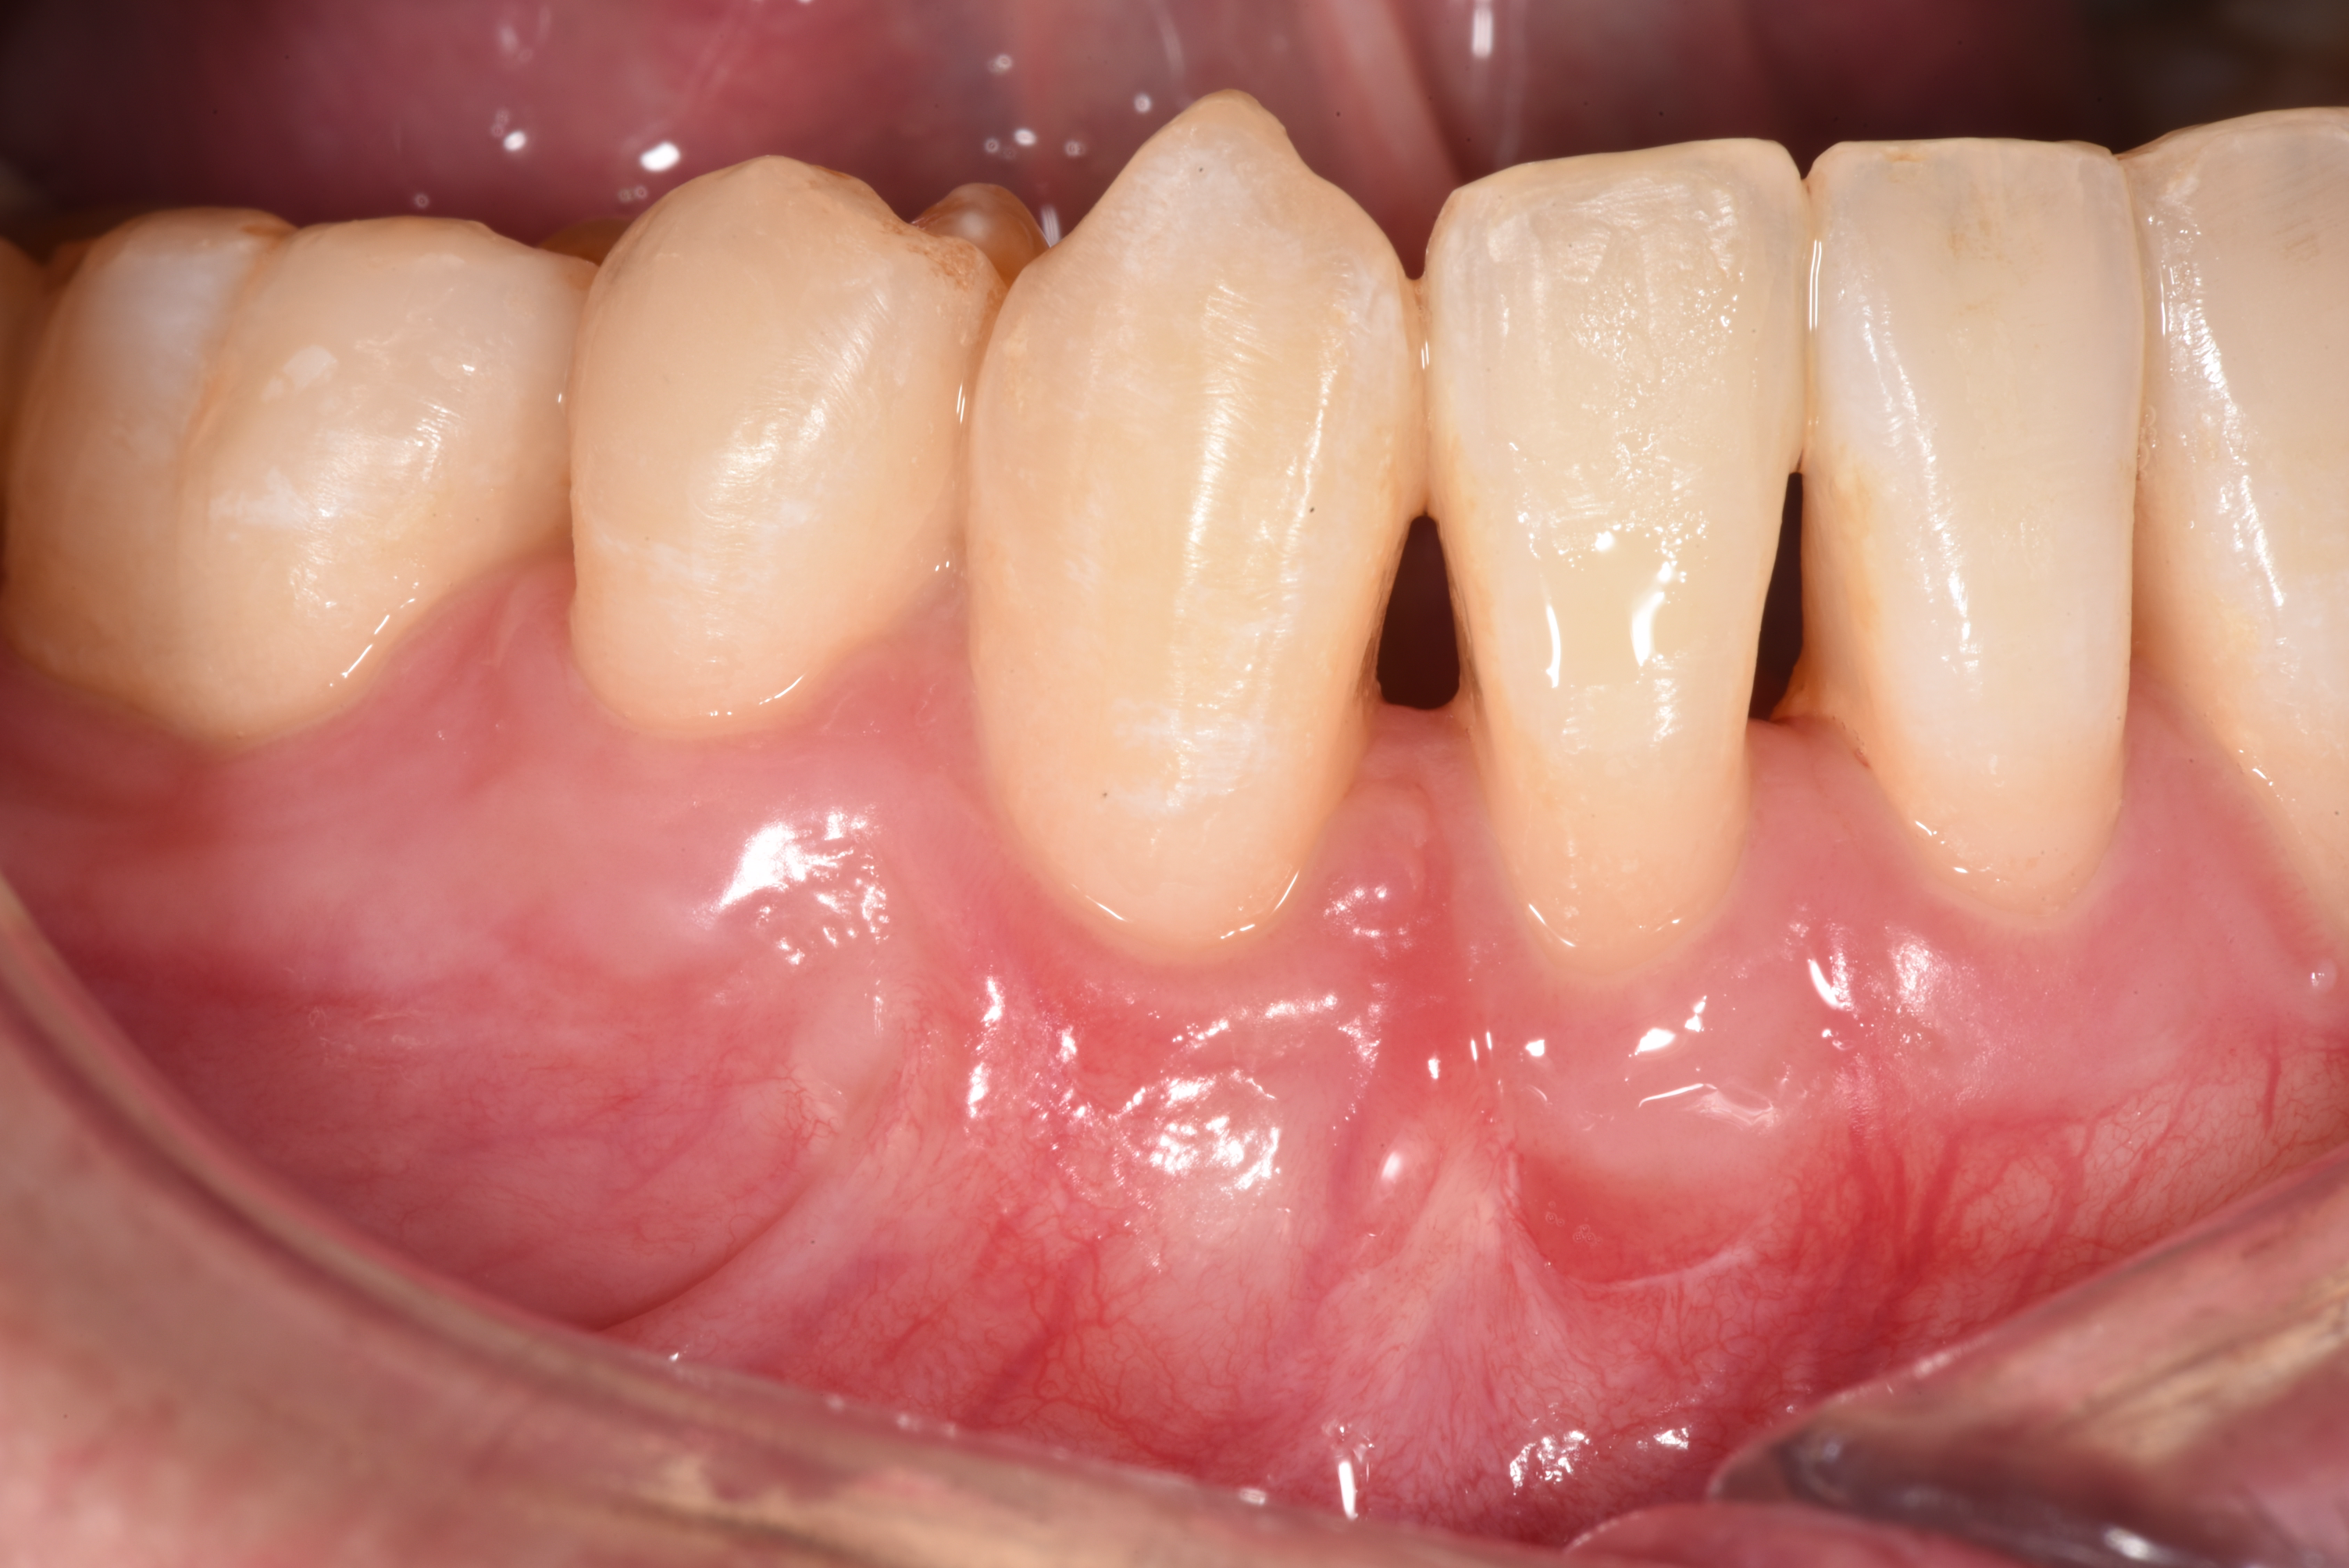

After gum surgery: the previously exposed root of the lower right canine is now almost completely covered